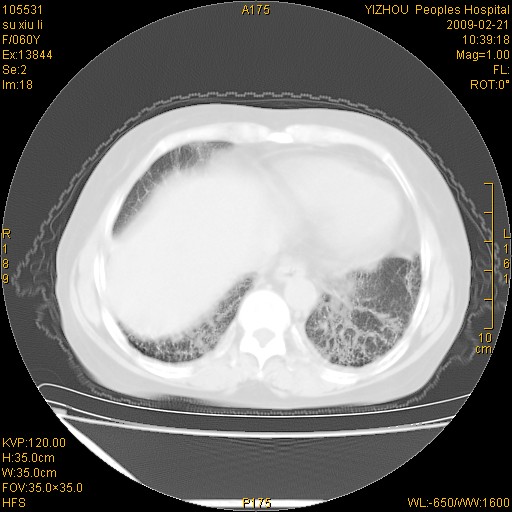

标题: CT18259:两肺间质纤维化? [打印本页]

标题: CT18259:两肺间质纤维化?

女,60岁,反复咳嗽1月。

两肺支扩,以肺为著合并双肺较广范纤维化病变。建议除外结核等病变。

两下肺支扩

符合间质感染,部分纤维化表现

特发性间质纤维化

特发性间质纤维化伴支扩!

间质性肺炎或特发性间质性肺炎